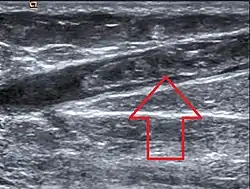

![]() صورة إشعاعية تظهر تخثر الوريد الصافن الكبير. صورة إشعاعية تظهر تخثر الوريد الصافن الكبير. | |